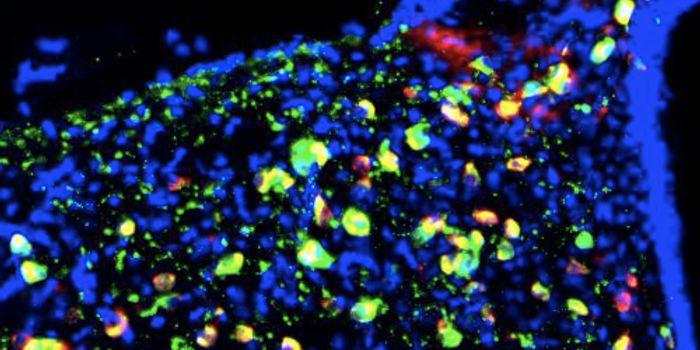

MAY 22, 2017ImmunologyThree new approaches to anticancer drug therapy were combined in a recent study to simultaneously maximize destruction o ...